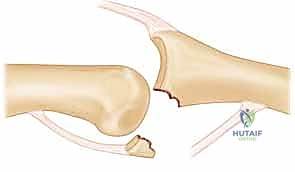

* FIG 2 • A. Avulsion fracture. Avulsion fractures usually are caused by a forced PIP joint hyperextension. The fragment is not comminuted and involves less than 30% of the joint surface. The PIP joint is most often stable.

* Impaction Shear Fracture-Dislocations:

* Mechanism: These are caused by a longitudinally applied load to the tip of the finger with the PIP joint slightly flexed, such as a "jammed finger" from a mishandled ball catch. The force drives the middle phalanx into and over the proximal phalanx head.

* Characteristics: This results in a middle phalangeal palmar lip fracture that is highly comminuted, with fragments often deeply impacted into the soft metaphyseal bone. Up to 80% of the joint surface can be involved.

* Stability: The joint reduction is often unstable.

*

* FIG 2 • B. Impaction shear fracture. This type of PIP fracture-dislocation is caused by a longitudinal load to the joint. The fracture fragments are comminuted and impacted into the middle phalanx. The joint reduction often is unstable.